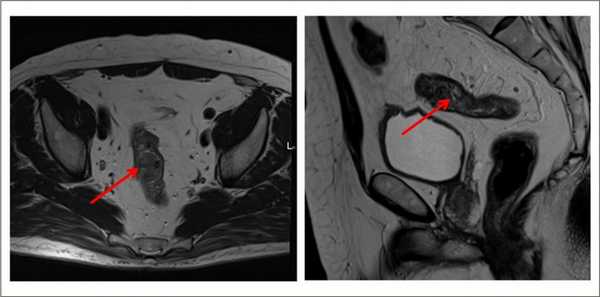

Как выглядит рак прямой кишки - фото

На фото рака прямой кишки можно заметить, что он значительно сужает просвет кишечника. Это является причиной запоров, переполненного живота, метеоризма.

На этом фото карцинома растет инфильтративно, охватывая стенку.

Выявляет даже небольшие по размеру патологические очаги, метастазы и инвазию опухоли в соседние органы, ее топографическое положение относительно других структур. Метод безопасен, не создает радиационную нагрузку, в отличие от КТ.